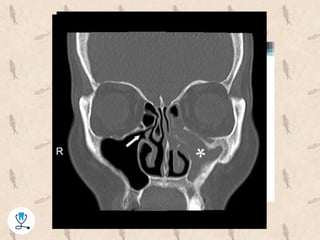

•‫منشاء‬20%‫ب‬ ‫می‬ ‫اپیکال‬ ‫پری‬ ‫یا‬ ‫پریودنتال‬ ‫عفونت‬ ، ‫ماگزیال‬ ‫های‬ ‫سینوزیت‬‫اشد‬

–‫ثانویه‬ ‫عفونت‬(‫است‬ ‫نادر‬ ‫و‬ ‫افتد‬ ‫می‬ ‫اتفاق‬ ‫کم‬ ‫خیلی‬)‫اوربیتال‬ ‫یا‬ ‫اوربیتال‬ ‫پری‬:

‫اوربیتال‬ ‫کف‬ ‫یا‬ ‫اتموئید‬ ‫سینوس‬ ‫طریق‬ ‫از‬

•‫کاورنوس‬ ‫سینوس‬ ‫سپتیک‬ ‫ترومبوز‬

–‫سینو‬ ‫به‬ ‫افتالمیک‬ ‫ورید‬ ‫یا‬ ‫اوربیتال‬ ‫ورید‬ ‫طریق‬ ‫از‬ ‫ماگزیال‬ ‫ادنتوژنیک‬ ‫عفونت‬ ‫ورود‬‫س‬

‫کاورنوس‬

–‫میشوند‬ ‫ترومبوز‬ ‫موجب‬ ‫نتیجه‬ ‫در‬ ‫و‬ ‫عروقی‬ ‫درون‬ ‫التهاب‬ ‫و‬ ‫ها‬ ‫باکتری‬ ‫تهاجم‬